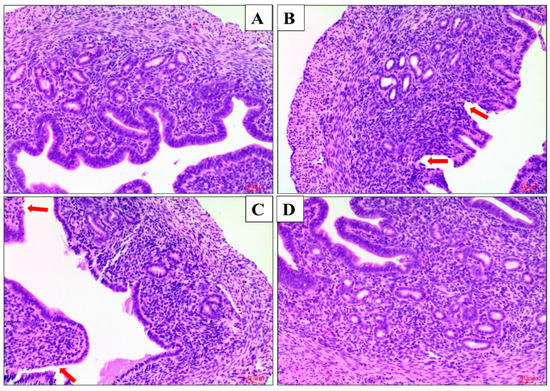

2.1. Effect of AS IV on LPS-Induced Histopathological Changes of Uterus